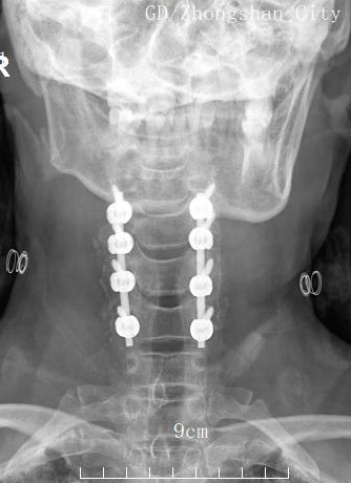

手術(shù)由程俊杰主任醫(yī)師主刀,在麻醉科和手術(shù)室的通力配合下,專家團(tuán)隊(duì)運(yùn)用超聲骨刀進(jìn)行了精準(zhǔn)截骨減壓。術(shù)中有效擴(kuò)大了狹窄的椎管,為受損的脊髓神經(jīng)創(chuàng)造了寶貴的復(fù)蘇空間。隨后,團(tuán)隊(duì)順利置入側(cè)塊螺釘內(nèi)固定系統(tǒng),位置精準(zhǔn)、固定牢靠,并進(jìn)行了關(guān)節(jié)突關(guān)節(jié)植骨融合。

術(shù)后X光片正位